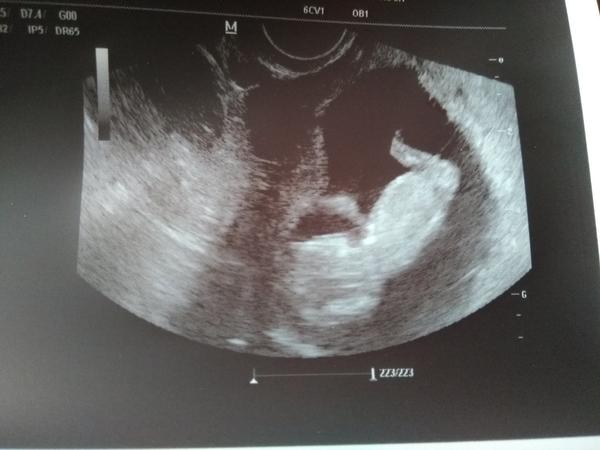

Ahojte ja dnes kontrola v centre... Mame dve ruky, dve nohy, srdiecko krasne bilo a mame 3,6cm. Tesime sa...V utorok dalsia kontrola u mojej gyn. snad uz aj knizka bude...

Ahojte baby ,takze dnešné sono dopadlo dobre, dostali sme aj tehotenskú knizku 🙂máme 3,34cm a krásne skákal v brušku keď ho pán doktor meral 😃

@ivankalaco Ahoj. My sa máme výborne 😀 žiadne tehotenské nevoľnosti, našťastie 😊 takže si užívame naplno 😀. V piatok sme mali kontrolu u dr. Drobec krásne rastie... 😁 Už máme 5,1cm.. Krásne hýbalo ručičkami a kopkalo nožičkami a skákalo ako žabka.. predviedlo sa mi v plnej paráde.. dnes sme už v 12+3tt. A termín pôrodu máme 09.03.2019.. Dr. povedala, že už si môžme vydýchnuť, že už to najhoršie máme za sebou.. vraj už sme za vodou.. tak sa hrozne tešíme 😀 ďalšiu kontrolu máme až 20.09., už teraz sa neviem dočkať, kedy drobca uvidím znova 😀 je to naozaj nádherný pocit 😊😊😊 Držím Vám všetkým palce, aby ste to každá raz zažila 😘😘